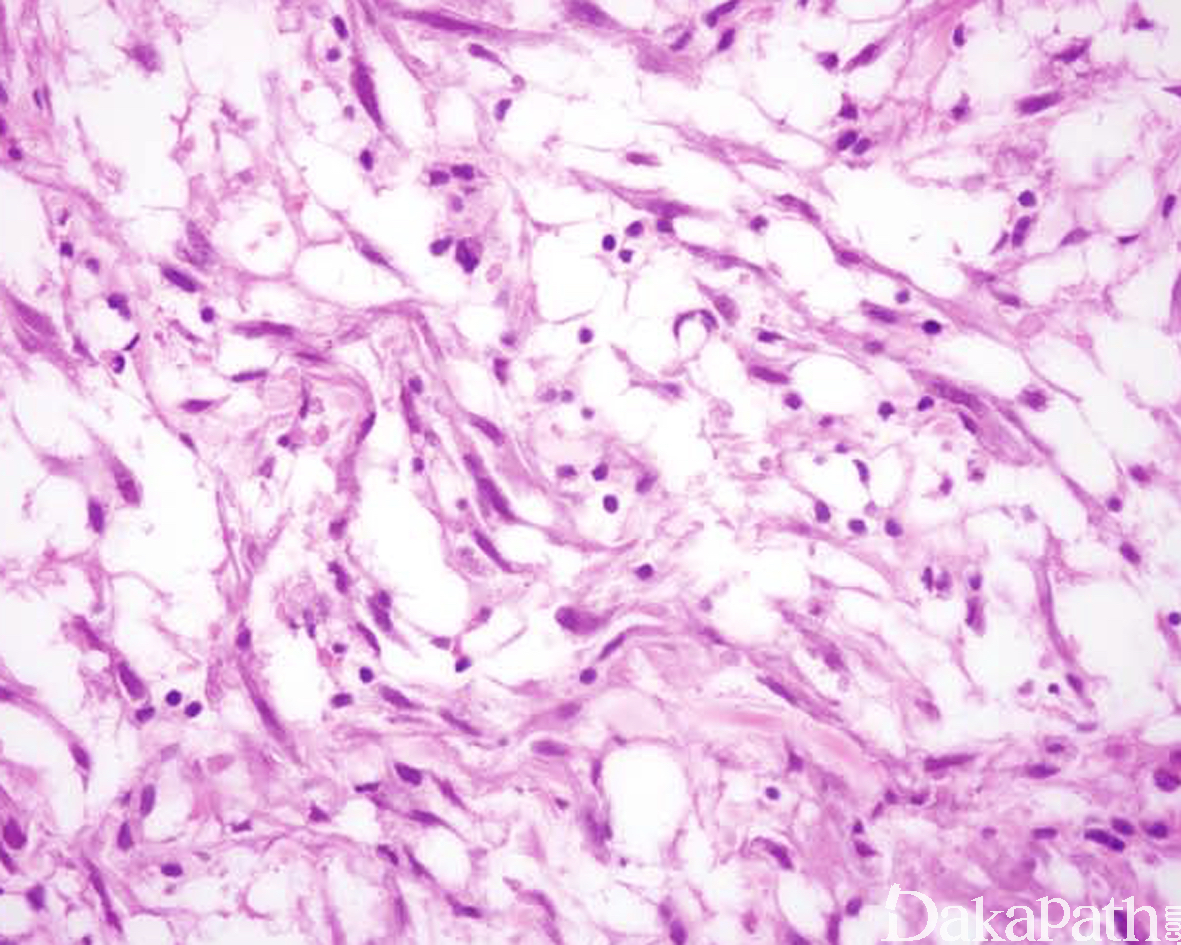

组织学上,IMT 由比例多少不等的梭形或多角形细胞、纤维/肌纤维母细胞以及淋巴浆细胞混合性组成,部分病例可见嗜酸性粒细胞和中性粒细胞浸润;

梭形细胞可见致密的席纹状或束状排列仅见少量的炎细胞浸润,亦可表现为广泛的炎性背景仅有少数梭形肿瘤细胞;

常见黏液性间质、少细胞区伴有丰富的毛细血管网以及局灶致密的胶原变性等组织学特征,偶见间质钙化;

梭形瘤细胞通常具有卵圆形至伸展的核,小而显著的嗜酸性核仁以及较丰富的双嗜性胞浆,有时候类似于萎缩的横纹肌细胞或神经节细胞;